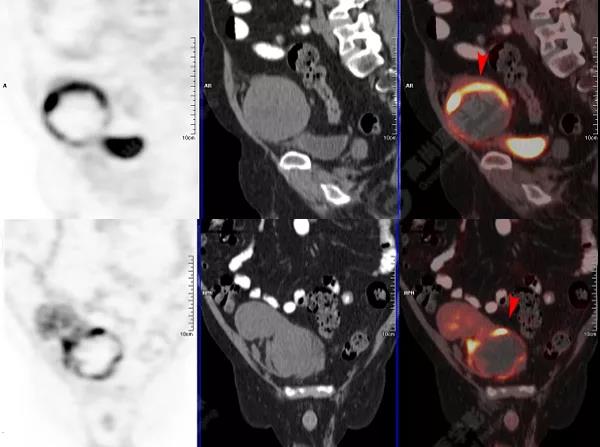

PET/CT檢查

↑移植腎下部等密度腫塊,代謝環(huán)狀增高,SUVmax13.4,中心代謝缺損

移植腎腫物穿刺活檢病理:移植后EBV陽性的彌漫大B細(xì)胞淋巴瘤。